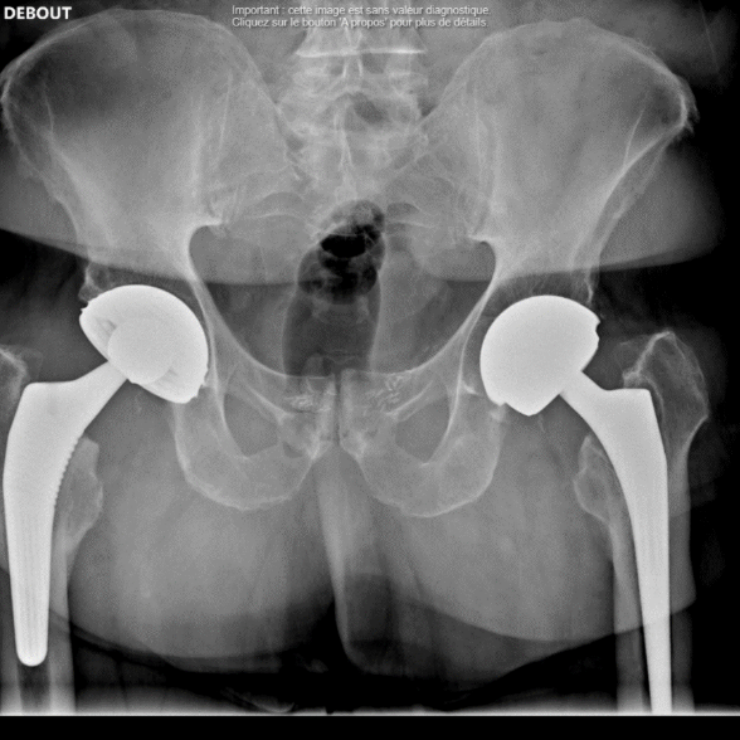

Chirurgie de la hanche

Voici les interventions les plus fréquemment réalisées par notre équipe sur cette articulation :